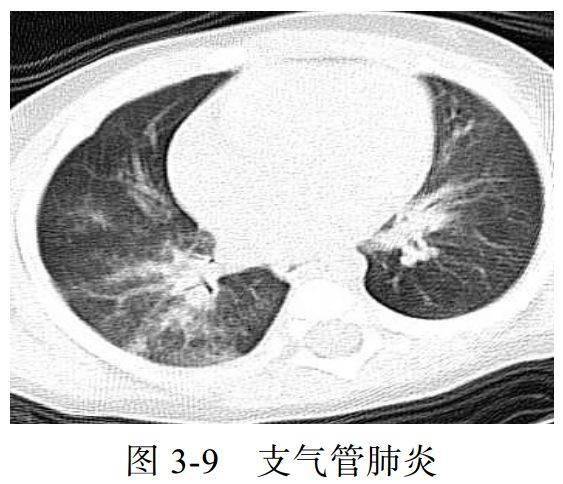

影像学表现:

(1)病变多分布于两肺中内带,可见沿支气管血管束分布的斑片、絮片、条索状影(图 3-9),出现树芽征

(2)病灶可融合成团片状,常伴有局限性肺气肿、肺不张